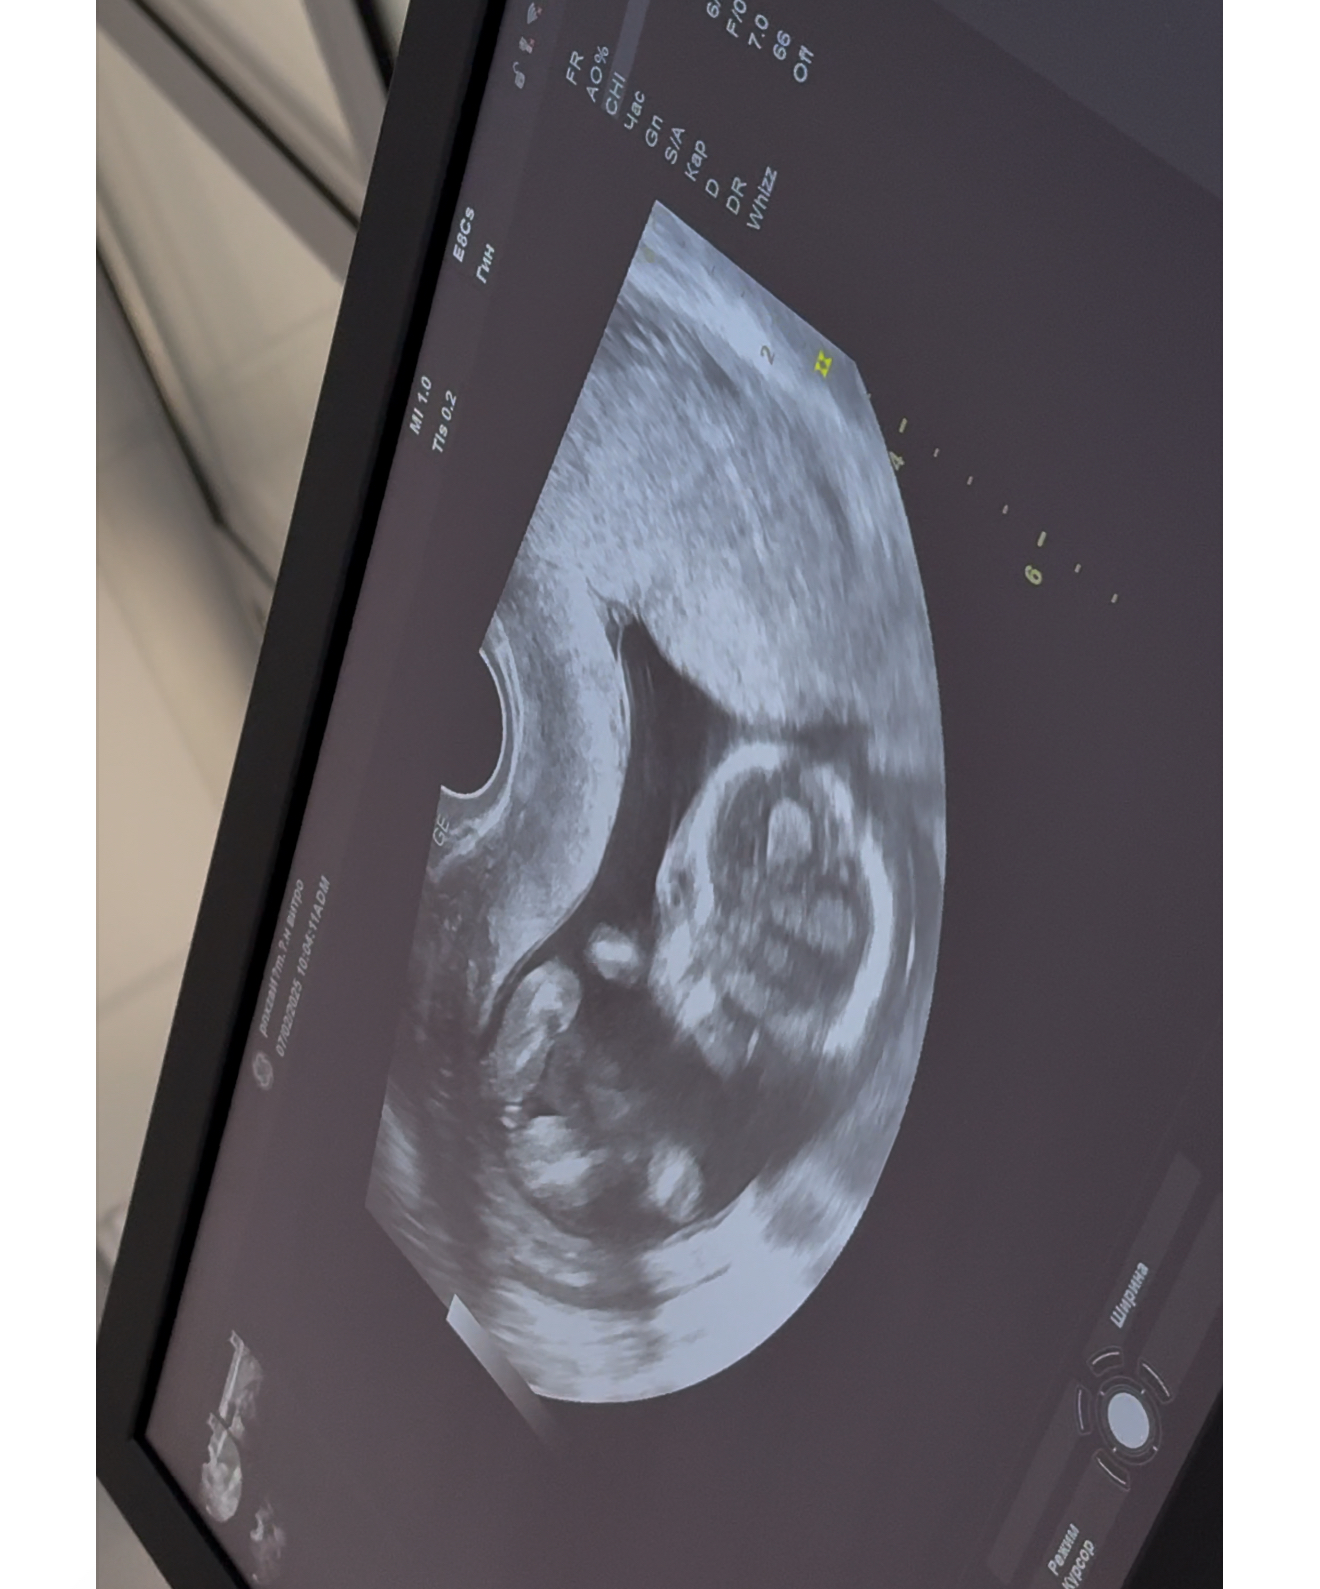

Кто в теме, подскажите пжста, веду беременность платно, на первом скрининге за пол я не спрашивала, так как понимала что срок маленький совсем. На 11 неделе делали. Далее перед отпуском решила сходить сделать узи платно, подсмотреть так сказать за малышом)) Было 14 - почти 15 недель. Я шла просто подсмотреть! А узист закончив первые важные замеры, спросила а не говорили ли мне уже пол? Я ответила что нет, маленький ведь срок. На что она мне сказала ну тут уже все очень даже видно, мальчик у вас будет! Заявила на все 100% и все оставшееся время пока мы там все рассматривали , ручки ножки, она раз 10 сказала что пистолетик видно 😂 Прям уверила . Но мне, честно, тоже показалось сразу это самое, как только началось узи. Фото приложу. И вот вернулась я с отпуск, думаю схожу еще раз , а то второй скрининг только 12 марта. И что вы думаете? В этот раз она молчала на счет пистолетика про который твердила в первый раз 🙈🫠 17 недель и 3 дня по последний мес 🩸 и по малышу написала 16 недель 9 дней. Как в аптеке 😅 Сказала что-то сегодня не видно ничего. Короче малость я расстроилась конечно.. когда тебя так сильно уверяли, а сегодня вот такое) Еще и фотку распечатала пистолетика, сказала мужу показать) эхх Все фото это 14-15 недель